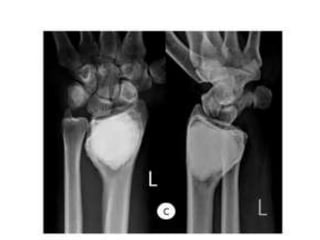

JULY 2009

SEPT 2009